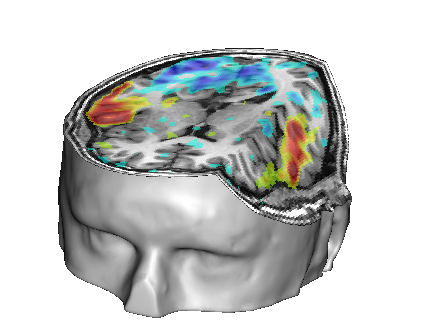

Fusion between an anatomical volume and an activation map

Load:

T1 MRI:

data_for_anatomist/subject01/subject01.niiActivation map:

data_for_anatomist/subject01/Audio-Video_T_map.nii

Fusion the 2 images. Note that they are not well superimposed because they are not in the same referential. But they are in Nifti format and contain information about a transformation to the referential Talairach-MNI Template-SPM.

For each volume, right-click Referential => Load information from file header.

Look at the fusion, the 2 images are now well superimposed.

Change the point of view by changing the referential of the window: click on the colored bar at the top of the window and choose Talairach-MNI Template-SPM. Notice the change of orientation.

Fusion between an activation map and a T1 MRI¶